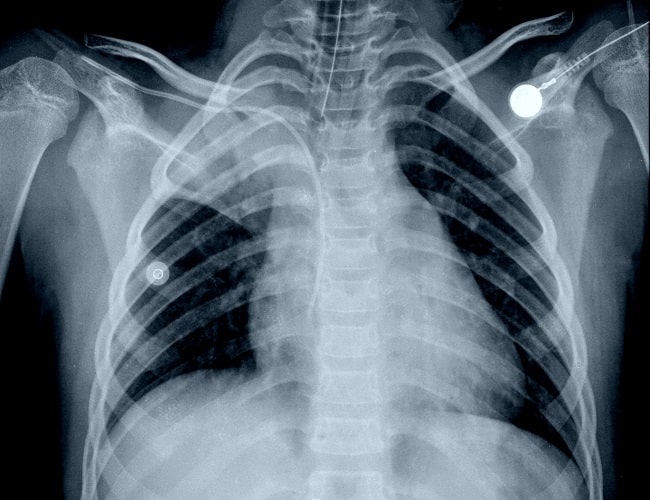

Diagnosis Atelektasis biasanya di lakukan melalui pemeriksaan rontgen dada, CT scan, atau bronchoskopi untuk mengetahui penyebab pasti dan luasnya kerusakan.